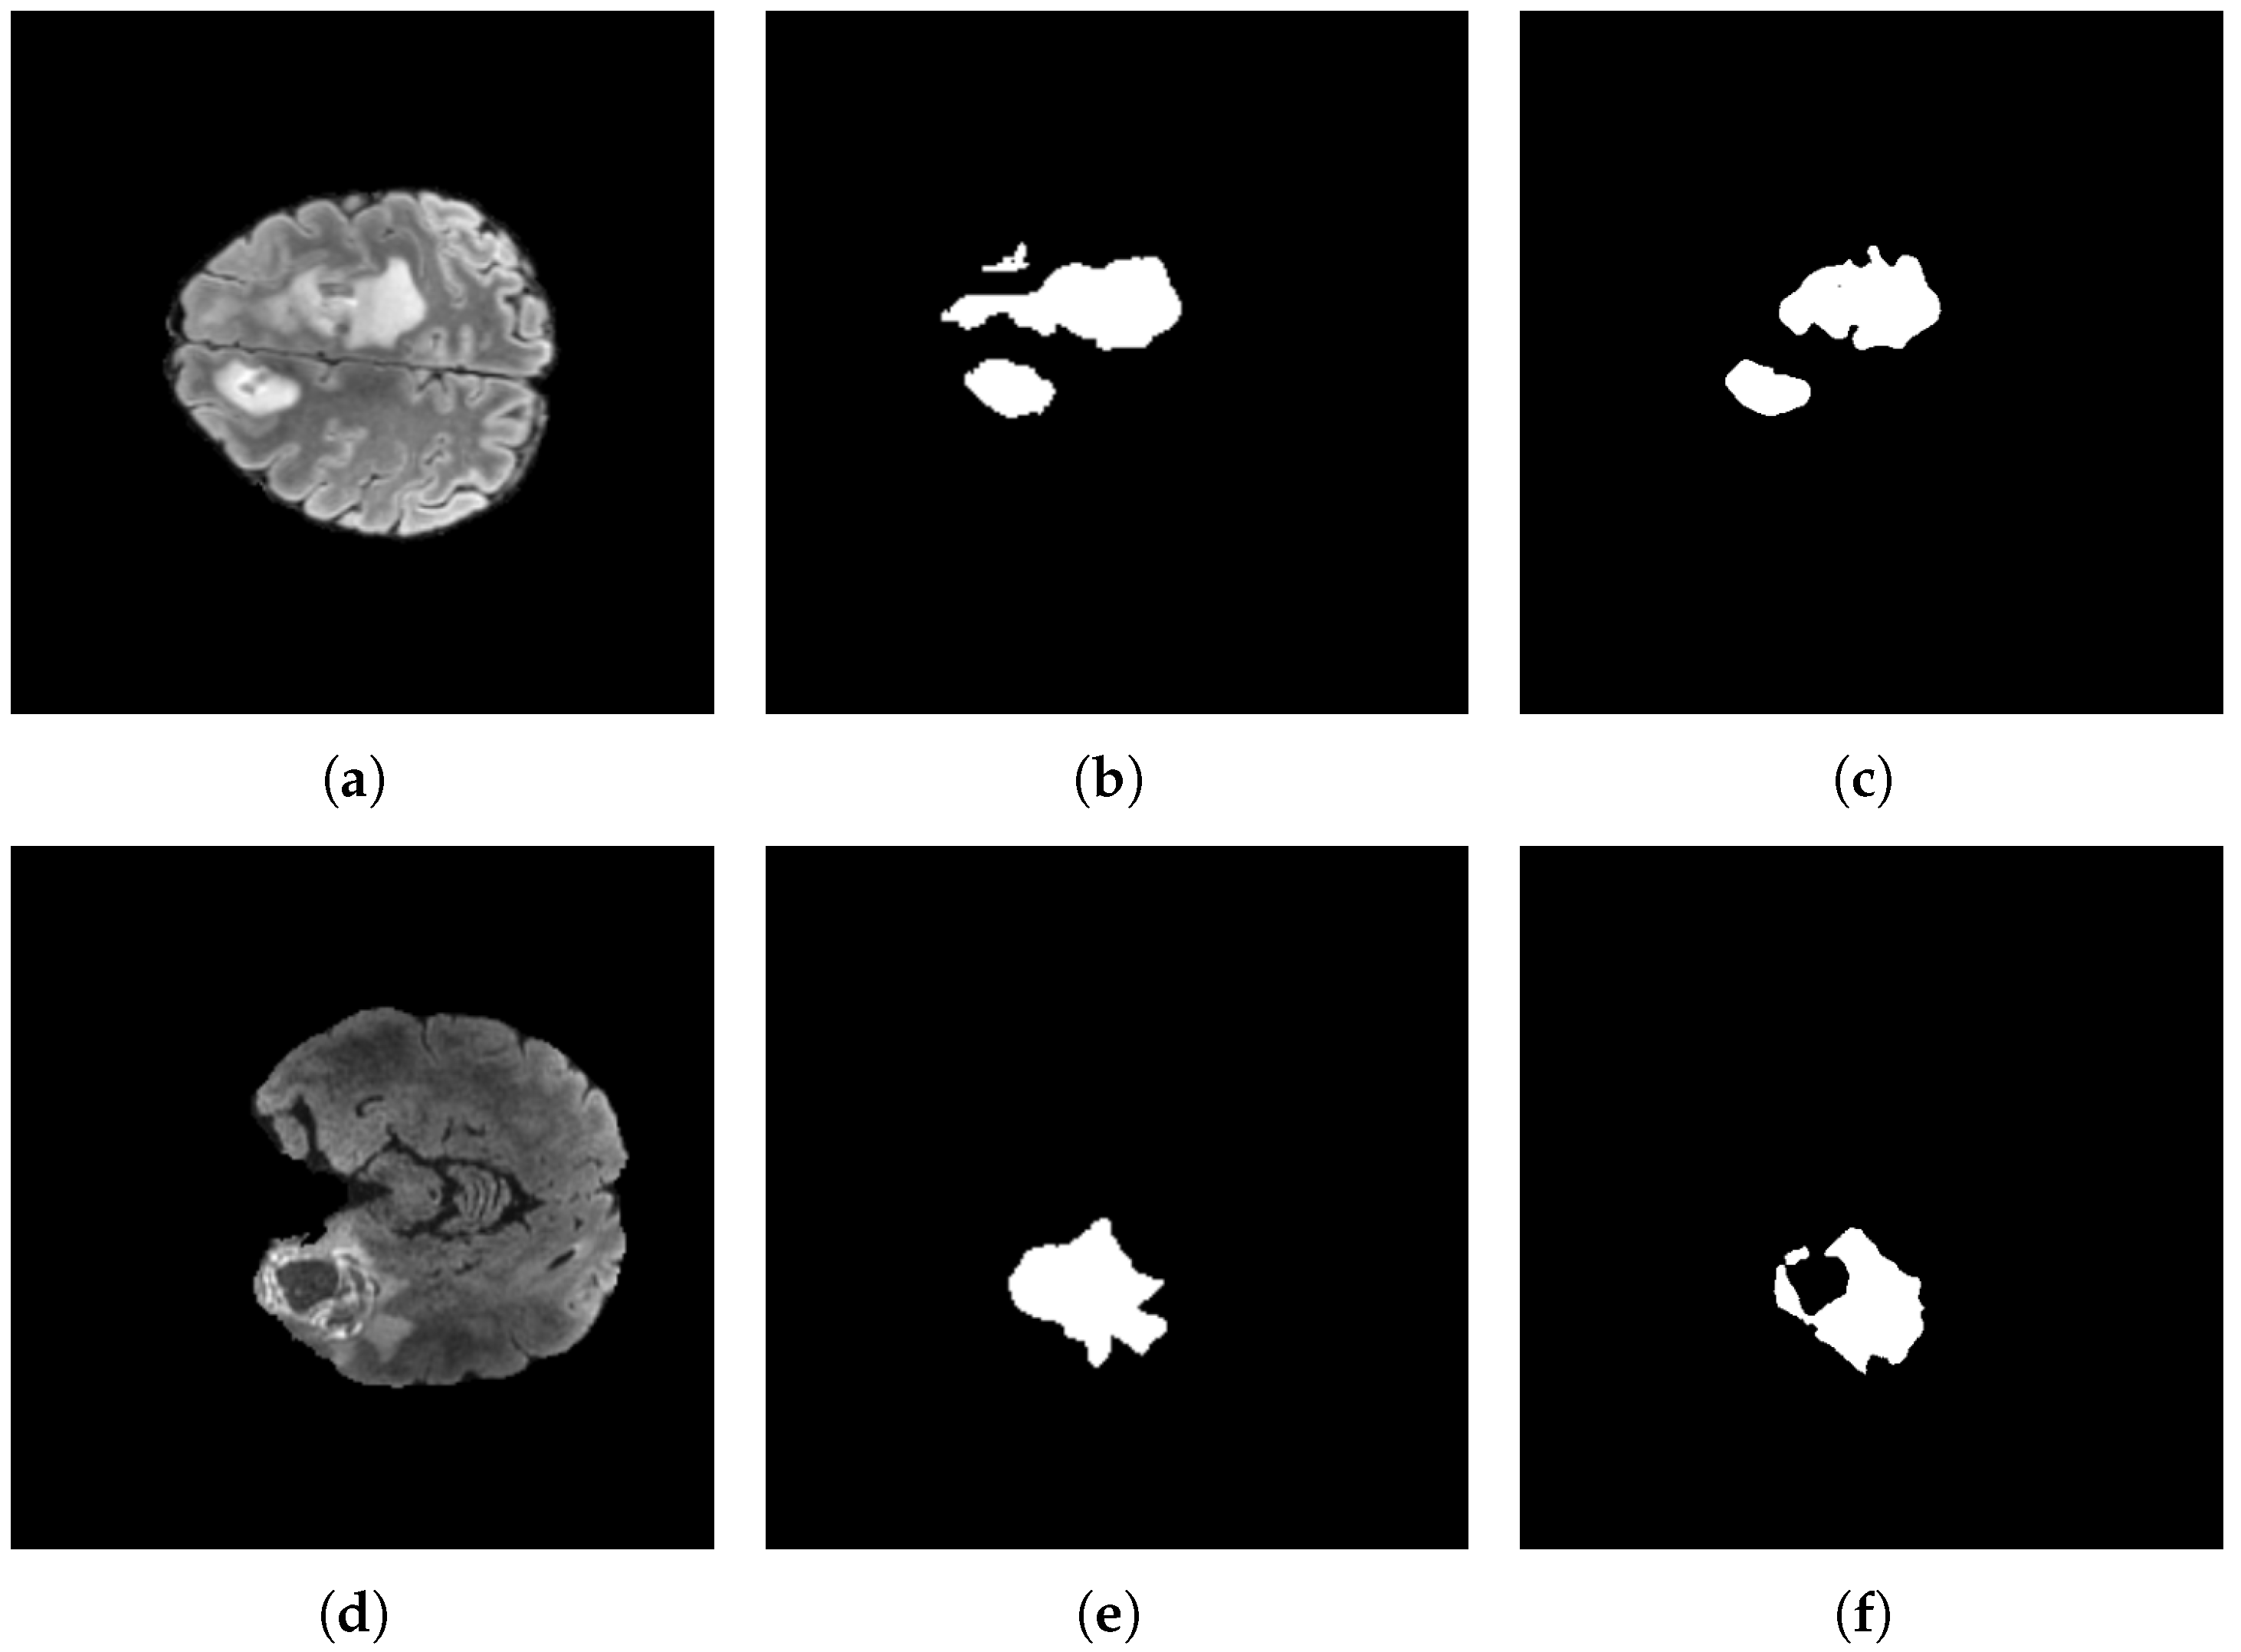

By contrast, Figure 17 presents low-rate recognition cases in which the model’s predictions are suboptimal. Although a non-negligible portion of the lesion is correctly highlighted, relevant regions remain missed. Notably, the errors predominantly manifest as conservative under-segmentation rather than false positives, with no spurious activations in unrelated tissue. This pattern suggests a bias toward precision over recall in these instances.